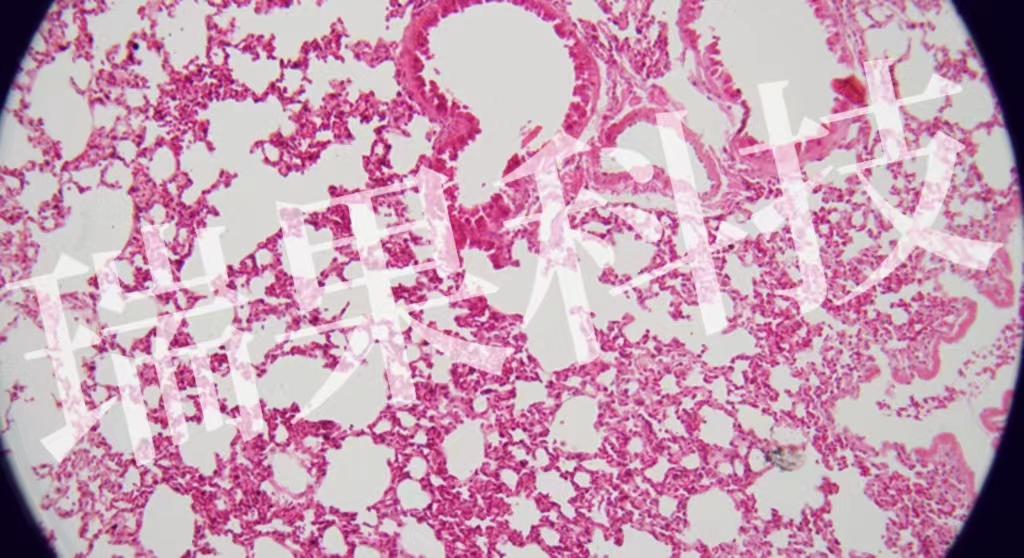

HE染色:苏木精 - 伊红染色法 ( hematoxylin-eosin staining ) ,简称HE染色法 ,石蜡切片技术里常用的染色法之一 。苏木精染液为碱性 ,主要使细胞核内的染色质与胞质内的核酸着紫蓝色 ;伊红为酸性染料 ,主要使细

HE染色:苏木精 - 伊红染色法 ( hematoxylin-eosin staining ) ,简称HE染色法 ,石蜡切片技术里常用的染色法之一 。苏木精染液为碱性 ,主要使细胞核内的染色质与胞质内的核酸着紫蓝色 ;伊红为酸性染料 ,主要使细胞质和细胞外基质中的成分着红色 。HE染色法是组织学、胚胎学、病理学教学与科研中最基本、使用最广泛的技术方法。